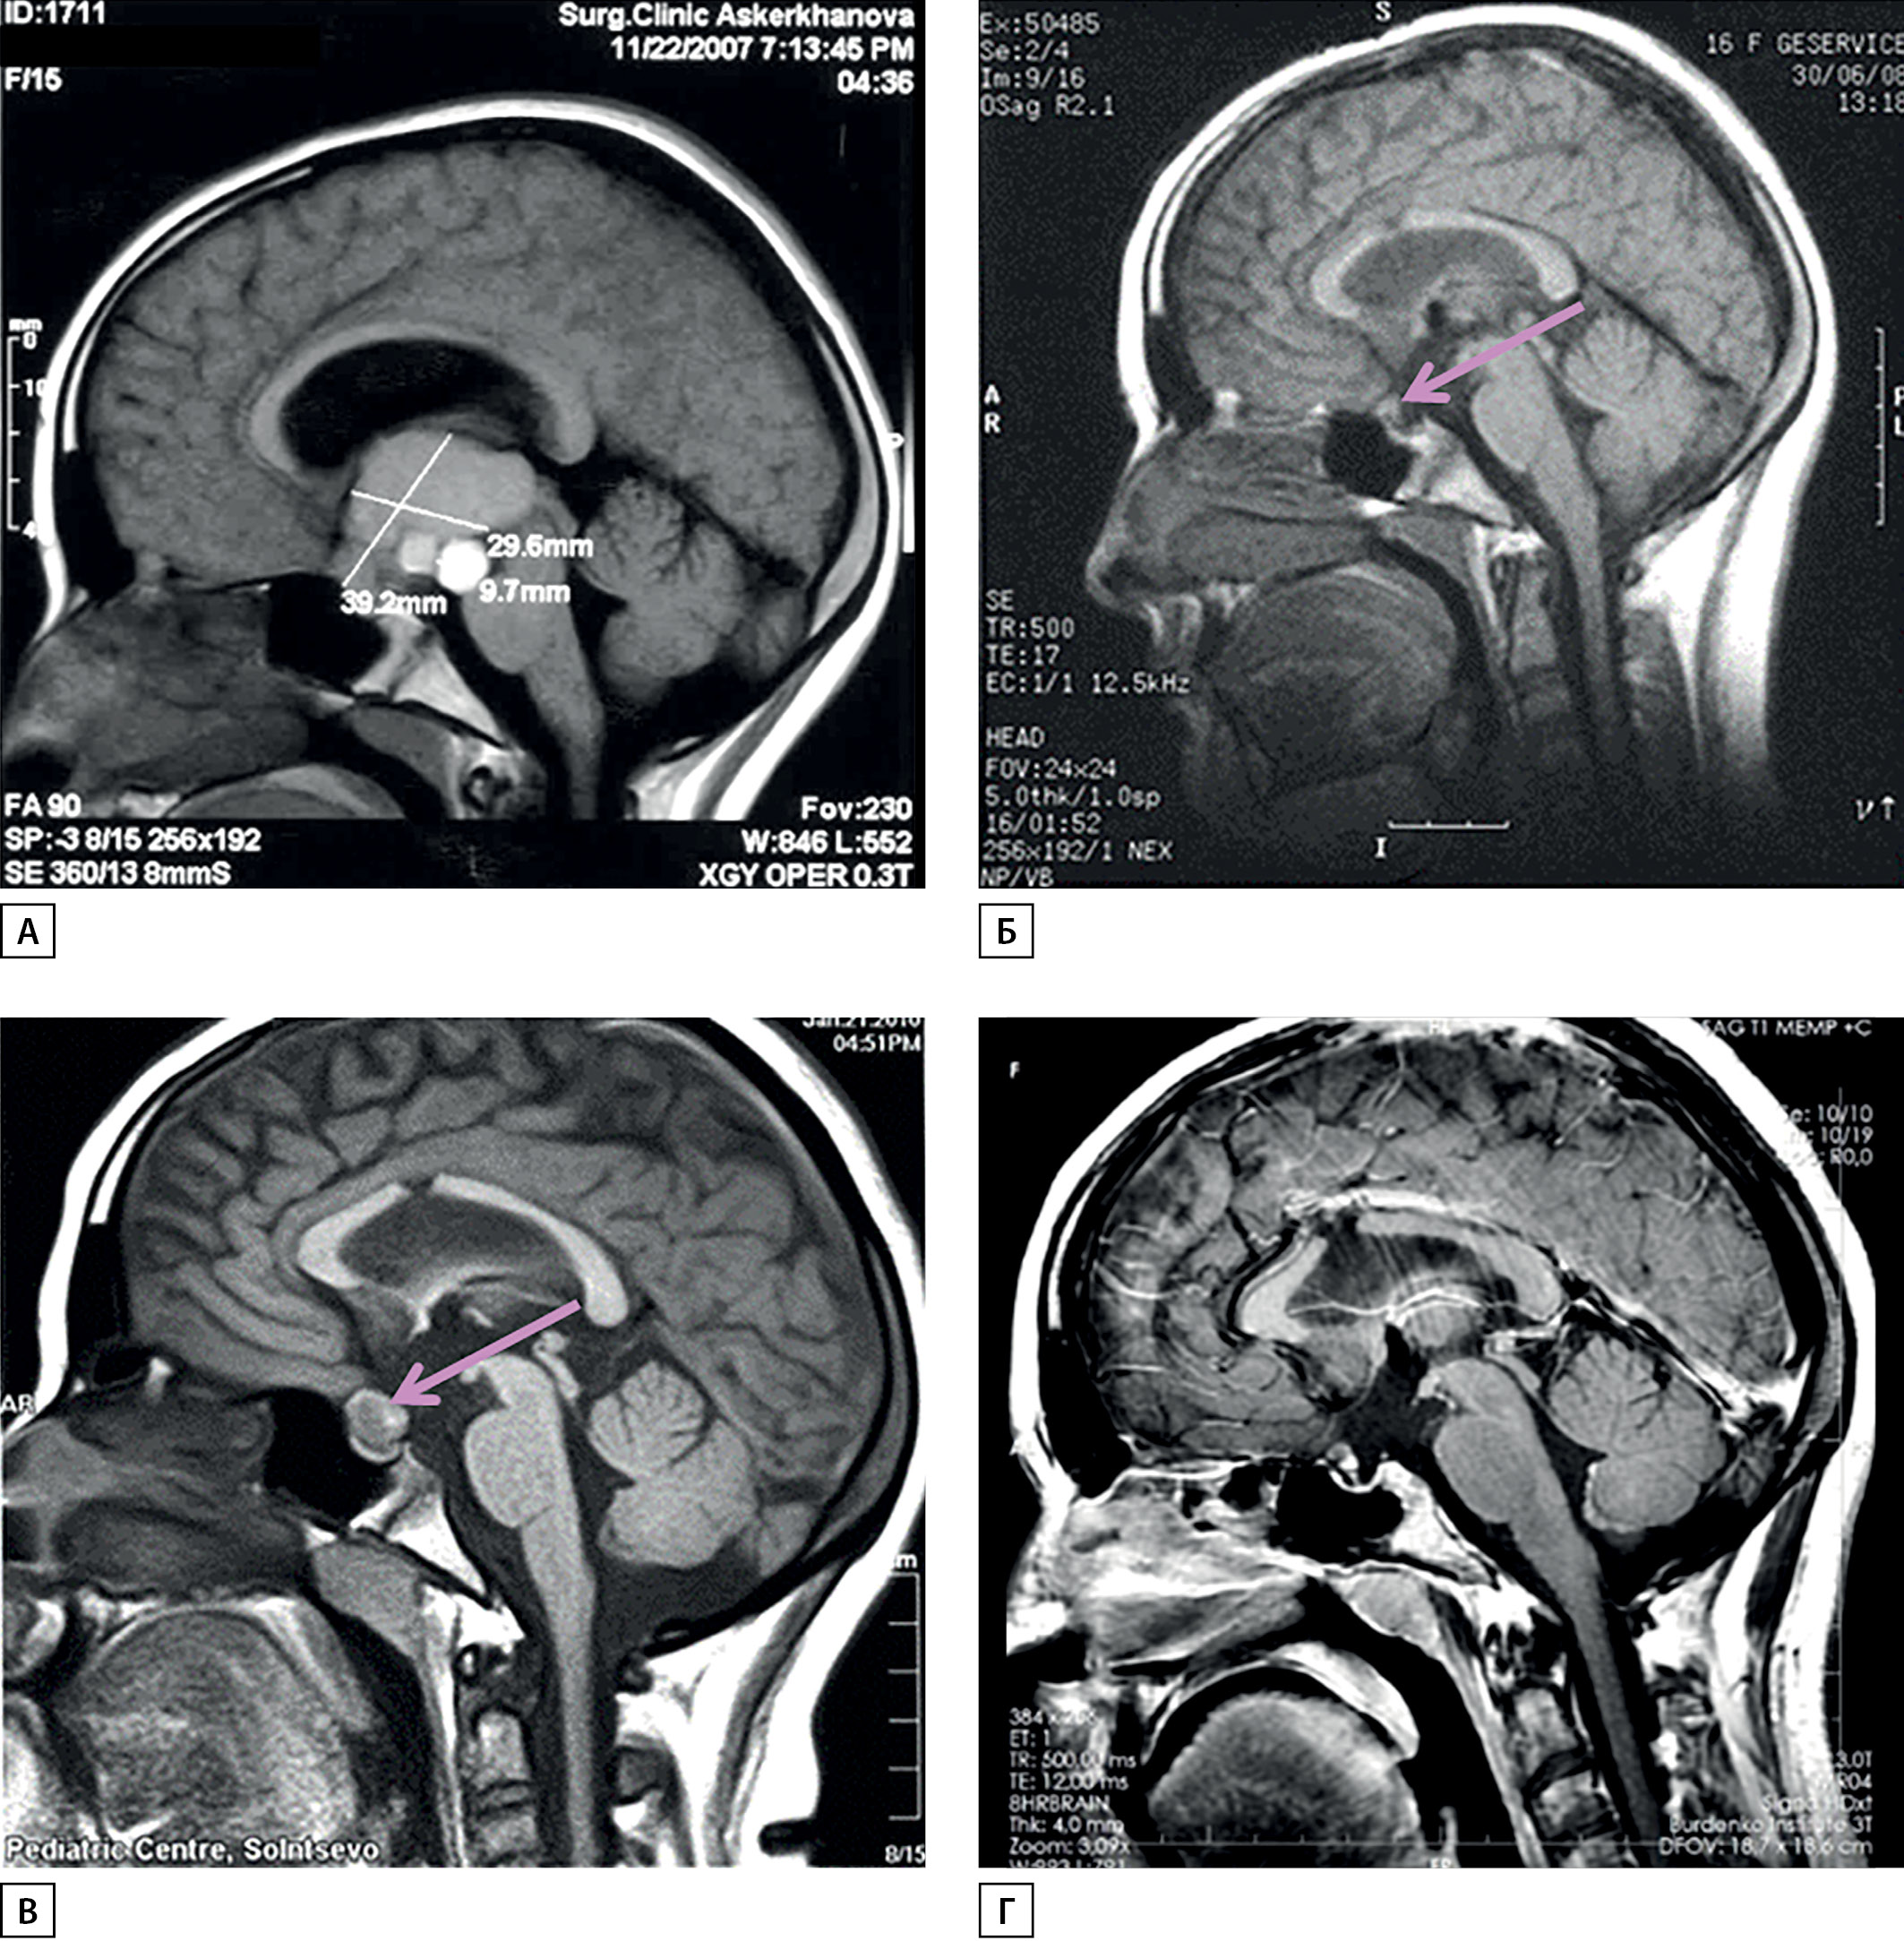

У пациентки А.Ш. с 13 лет отмечены замедление роста и остановка полового созревания. В 15 лет появились головные боли, к которым через несколько месяцев присоединились рвота, снижение остроты зрения до 0,4 на оба глаза, правосторонняя гомонимная гемианопсия. При МРТ выявлена мультикистозная интраэкстравентрикулярная КФ (рис. 1А), окклюзионная гидроцефалия. В январе 2008 г. (15,9 года) поступила в НМИЦ нейрохирургии им. академика Н.Н. Бурденко для хирургического лечения.

Больная была оперирована — проведено субтотальное удаление опухоли комбинированным доступом (транскаллезным и птериональным) (рис. 1Б). После операции развился НД, назначен десмопрессин. Ранний послеоперационный период протекал тяжело — отмечались электролитные расстройства (уровень натрия колебался в пределах 125–155 нМ/л), в течение 2 нед проводилась интенсивная терапия в реанимационном отделении. После стабилизации показателей электролитного обмена девочка выписана.

В феврале 2010 г. (через 2 года после хирургического лечения) при очередной контрольной МРТ выявлен рецидив опухоли небольших размеров, расположенный эндосупраселлярно (рис. 1В). Проведено стереотаксическое радиохирургическое лечение на аппарате Гамма-нож с предписанной дозой 12 Гр, предписанной изодозой 50% на мишень объемом 1,1 см3. В динамике после облучения остаток опухоли уменьшился (рис. 1Г).

Рисунок 1. МРТ головного мозга пациентки в динамике.

А — до операции; Б — через 6 мес после субтотального удаления краниофарингиомы (определяется небольшой остаток опухоли в хиазмально-селлярной области); В — рецидив опухоли (увеличение остатка) через 2 года после удаления перед радиохирургическим лечением; Г — уменьшение остатка опухоли через год после радиохирургического лечения.

1. Рисунок 1. МРТ головного мозга пациентки в динамике. А — до операции. ; Б — через 6 месяцев после субтотального удаления КФ краниофарингиомы (определяется небольшой остаток опухоли в хиазмально-селлярной области). ); В — рецидив опухоли (увеличение остатка) через 2 года после удаления перед радиохирургическим лечением. ; Г — уменьшение остатка опухоли через год после радиохирургического лечения. | |